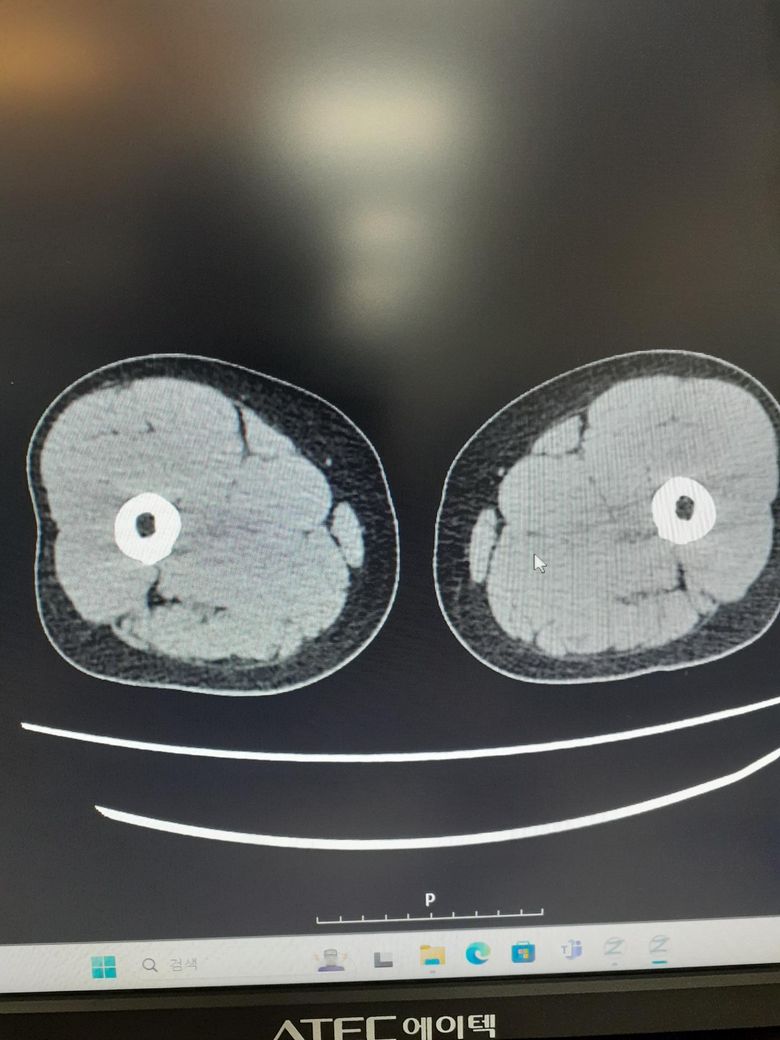

ct사진좀봐주세요사례합니다 조영제십니다

• 1번 째 사진